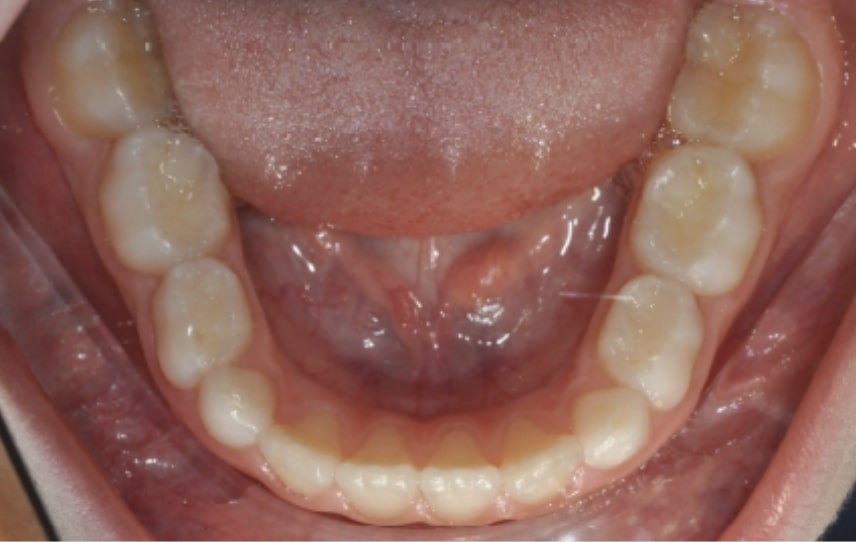

Malocclusion A6 Correction of Mandibular Retrusion in Growth phase patient | Skeletal Class II | Class II Division 1 malocclusion | Deep bite | Mixed dentition

Initial Photos and datas

Clinical examination and diagnosis

DENTAL:

- Molar and Canine class 2 on the right side – Molar and Canine clss 1 on the left side

- Upper diastema (11-21)

- Increased Overjet

- DeepBite

- Reduced Transversal Diameters

- Deviated Lower Midline 2 mm to the Right